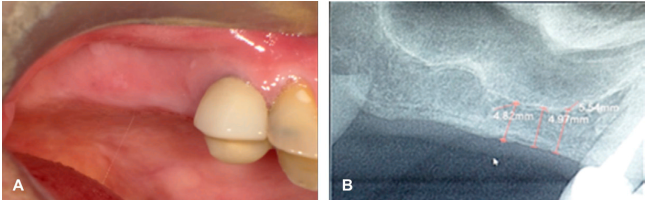

En la valoración intraoral se observa ausencia clínica y radiográfica de los dientes 15 y 16, disminución de altura ósea del reborde alveolar en la zona de premolares, presenta un tipo de reborde según Seibert tipo II, lo cual es una limitación para la colocación de implantes con el método convencional de rehabilitación (Figura 1 A-B). La radiografía digital evidenció la escasa altura ósea, revelando una altura promedio de 4.90 mm desde la cresta alveolar al piso de seno maxilar para la colocación de un implante (Figura 1B). Como plan de tratamiento se sugirió una cirugía atraumática, como la elevación transalveolar del seno maxilar con carga inmediata utilizando implante dental corto. Se ordenaron exámenes de laboratorio paraclínicos, los cuales mostraron el estado general del paciente en valores normales, lo cual permitió programar de la cirugía.

B. Radiografía digital donde se observa la poca altura ósea con respecto al piso del seno maxilar.

Figura 1 Fotografías iniciales. A. Fotografía clínica de tejidos blandos saludables.